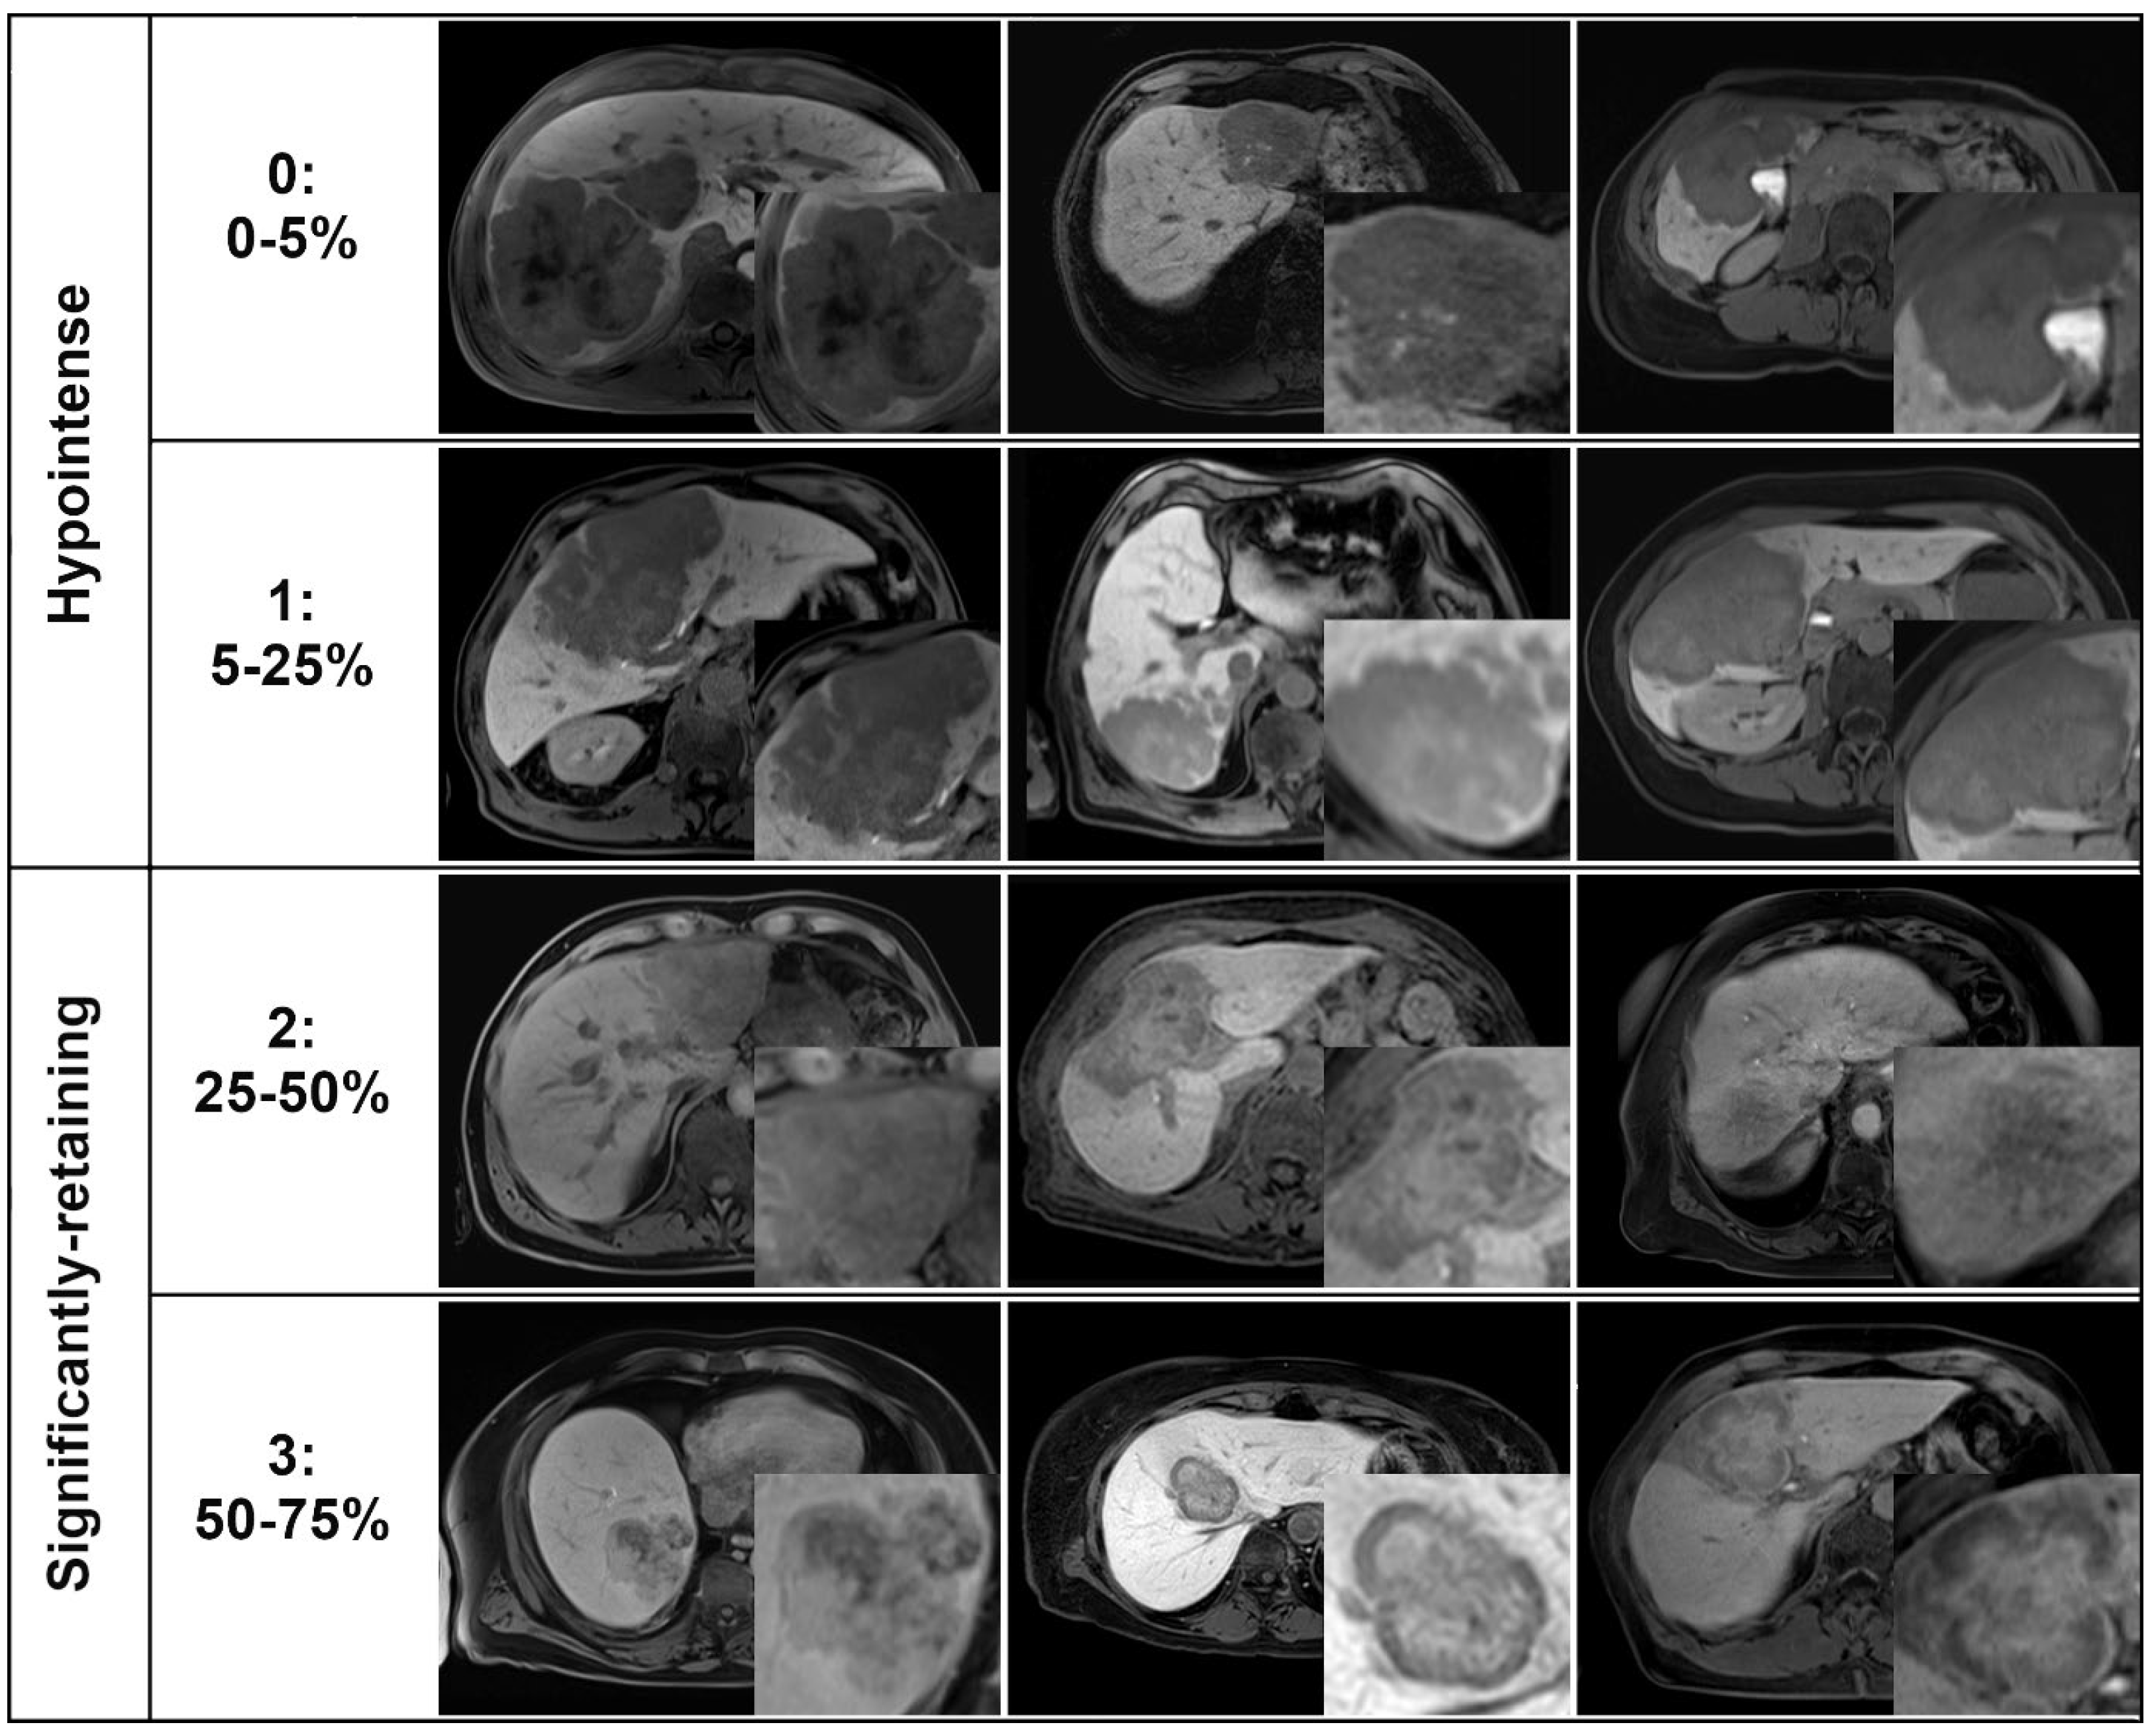

| Gd-EOB retention area | N/A | ||

| 0 (0–5%) | 19% (9/47) | 0% (0/19) | |

| 1 (5–25%) | 81% (38/47) | 0% (0/19) | |

| 2 (25–50%) | 0% (0/47) | 42% (8/19) | |

| 3 (50–75%) | 0% (0/47) | 58% (11/19) | |

| 4 (75–100%) | 0% (0/47) | 0% (0/19) | |